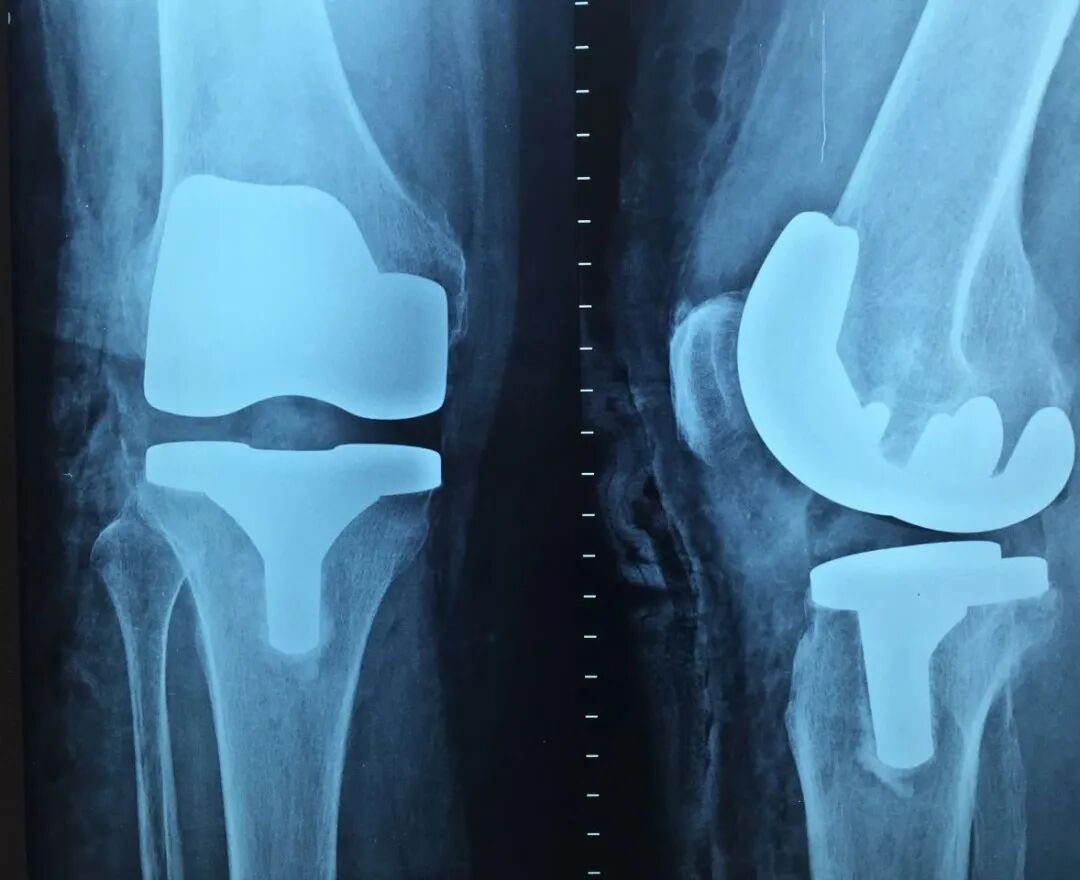

# CT检查 #

# CT检查是什么 #

CT即电子计算机断层扫描,它是利用精确准直的X线束、γ射线、超声波等,与灵敏度极高的探测器一同围绕人体的某一部位作一个接一个的断面扫描,供完整的三维信息,具有扫描时间快,图像清晰等特点,可用于多种疾病的检查。

CT的辐射剂量相较于X光片大一点,普通健康体检检查尽量选择低剂量CT筛查而不是常规CT,怀孕妇女不宜进行CT检查。

肺部CT 检查

CT检查目前有两种检查方式

1、普通平扫

即常规的CT检查,一般只需要躺在CT机上面进行扫描便可,无需打造影剂,速度快,方便简洁,故常作为初次检查、急性病变的首要检查方案。

2、增强扫描

在平扫CT的基础上,静脉注射造影剂(常用碘对比剂),通过血液循环跑到全身组织器官中,相当于给平扫的CT润色一番,有助于更加准确地分辨血液循环丰富的器官组织病变,如肿瘤。

一般来说,如果普通平扫CT能看清楚病变,并能做出明确的影像学诊断,那就不需要进一步做增强CT了,否则,需要完善增强CT以明确诊断。

极少部分人会对造影剂有不良反应,故检查时需要医护人员及家属或朋友陪同。

CT检查的作用

1

头部 脑出血、脑梗塞、动脉瘤、血管畸形、各种肿瘤、外伤、出血、骨折、先天畸形等可清楚显示脑挫裂伤、急性脑内血肿、硬膜外及硬膜下血肿、颅面骨骨折、颅内金属异物等,而且比其它任何方法都要敏感。CT诊断急性脑血管疾病如高血压脑出血、蛛网膜下腔出血、脑动脉瘤及动静脉畸形破裂出血、脑梗塞等有很高价值,急性出血可考虑作为首选检查。

2

胸部 肺、胸膜及纵膈各种肿瘤、肺结核、肺炎、支气管扩张、肺脓肿、囊肿、肺不张、气胸、骨折等;对于显示肺部病变有非常满意的效果,对肺部创伤、感染性病变、肿瘤等均匀有很高的诊断价值。对于纵隔内的肿物、淋巴结以及胸膜病变等的显示非常清晰也令人满意,可以显示肺内团块与纵隔关系等。

3

腹、盆腔:各种实质器官的肿瘤,外伤,出血、肝硬化、胆结石、泌尿结石、积水、膀胱、前列腺病变、某些炎症、畸形等能清晰的显示解剖的准确部位病变程度,对病变分期等有较高价值,有助于临床制定治疗方案,尤其对于手术科室的手术定位有重要意义。

4

脊柱、四肢:骨折。外伤。骨质增生、椎间盘病变、椎管狭窄、肿瘤、结核等;观察肿瘤向软组织浸润的情况,骨折、外伤、椎间盘病变等可以显示细小关节面的病变。

5

肝脏病变;CT检查对于肝内点位性病变、原发性肝癌或转移性肝癌的形态、轮廓、坏死、出血及生长方式等都可以显示,还可以了解胆、胰、肾等脏器的情况,所以慢性肝炎、肝硬化并存在可疑病变或肝癌的患者,非常有做CT检查的必要。肝CT检查对于早期肝硬化的诊断灵敏度较高。

6

心血管系统: 可用于心包肿瘤、心包积液等的诊断,急性主动脉夹层动脉瘤CT有肯定的诊断意义,特别是增强扫描具有特征性表现,并可做定性诊断。

CT检查注意事项

1 CT有辐射,对身体健康危害大吗?

CT检查会有辐射,但作为目前必要的医疗手段,它往往不可或缺,且遵循正规检查原则偶尔进行一两次检查并不会对健康造成显著影响。

此外,国家对各种检查中的辐射剂量有严格的管理标准,由专业放射科医师按规程操作,将放射强度和接触距离控制在标准范围内,注意对非检查部位和敏感器官进行屏蔽防护,不容易伤及受检者身体。随着X线技术的不断发展,检查设备也在不断更新,参数在不断优化,例如低剂量CT的发展就明显降低了CT的辐射剂量。

2 不适宜人群

一般来说,有几类人群不适合做ct检查,分别是幼儿患者、孕妇患者、心脏病患者、糖尿病患者、肾功能不齐全患者以及过敏体质患者。如果属于此类人群,一定要格外注意,不要强行进行CT检查,否则的话可能会加重身体不适,影响健康恢复,如有必要先考虑低剂量CT。

3 CT检查注意事项有哪些?

做CT检查前患者需要禁食,尽量排空肠胃内食物,以免影响检查结果。除此,患者还要注意检查前不能进行剧烈运动,也不能长时间运动,否则的话将会出现检查不准确的情况。

检查前患者还要注意排空小便,这样可以更清晰的观察膀胱内x显像,减少误诊和漏诊的情况。除了要注意这一方面之外,在检查前患者还要将身上的所有金属物品摘除,以免影响检查结果

检查时患者还要注意心情放松,不要说话,不要乱动,严格的按照医生的嘱咐进行,只有这样才能确定CT检查的准确性,

最常用CT、核磁急性中风、脊柱外伤先做CT,详细分析时可用核磁

脑和脊髓

最常用核磁,其次是CT

脊柱(颈椎、腰椎、胸椎)

最常用X光片、CT大致了解选X光片,细致分析选CT肺的检查一般不选核磁

最常用X光片

诊断不明确,可用CT

骨骼、四肢